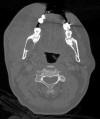

CT scan

Imaging:

• The panoramic view and the CT scan demonstrated a unlilocular, well demarcated, radiolucent lesion in the posterior aspect of the mandible. The rim of the lesion is smooth. There is no calcification at the center of the lesion.